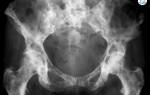

Важно понимать, что сколиоз — это искривление не только самого позвоночника, но и всей грудной клетки. У людей, страдающих сколиозом, часто наблюдается выступание ребер или лопаточной кости с одной стороны. Из-за такого нарушения симметрии очень часто возникает неправильное расположение органов грудной, а иногда и брюшной полости.